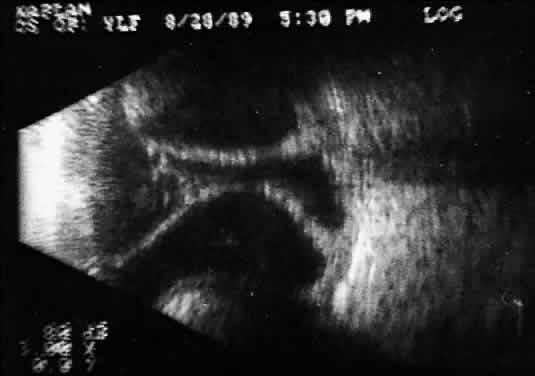

tissue characterization. The B-scan image, a two-dimensional crosssectional display of the globe and orbit, is more easily interpreted than A-scan, especially by examiners familiar with interpretation of ophthalmic pathology, where microscopic and gross crosssectional evaluation of the globe and orbit are routine and often topographically similar to B-scan cross-sections. Several concepts are critical to accurate interpretation of B-scans. These concepts, although relatively easy to define, require considerable experience before the examiner feels comfortable with diagnosis in opaque media situations. These concepts are real time, gray scale, and threedimensional thinking. Real time refers to the display of motion or movement during B-scan imaging. This capability is one of the greatest advantages of B-scan. Differences in mobility of a variety of movable intraocular abnormalities can be easily detected. For example, the rapid movement of vitreous hemorrhage is usually easy to appreciate and differentiate from the slower, undulating movements of a recent, rhegmatogenous retinal detachment. On occasion, movement of intraocular structures can be used for detecting abnormalities that lie immediately behind vitreous opacification and may be seen only when the vitreous opacities are moved away from the ocular wall, set in motion by command voluntary movements of the patient's globe (Fig. 5). Gray scale refers to the variable gray tone of display screen echoes. Strong returning signals (echoes) appear white, whereas weaker reflections are seen as gray, the shade depending on echo strength. Examples of strong reflectors of sound include retinal tissue, sclera, and calcifications of any type (Fig. 6). Weaker echoes from clotted or clumped cells within the vitreous are usually easy to differentiate from the stronger reflectors of sound (Fig. 7). Grading of echo strength may be performed only when the examining ultrasound beam is perpendicular to the object of interest, ensuring the strongest possible reflections. However, in the world of ultrasound interpretation, there are many exception to the rules. Tissues that are usually mild reflectors of sound, such as hemorrhage, can at times appear quite strong, especially in complex or multiple pattern disorders, as frequently occur in severe ocular trauma. These apparent inconsistencies often cause misinterpretation by the novice. With experience obtained by multiple examinations, careful follow-up, and clinical correlation whenever possible, diagnostic acumen rapidly improves.

3D thinking is the third B-scan concept necessary for accurate interpretation, and the most difficult to master. During B-scan examinations, the contact probe is almost always in motion, creating multiple, ever-changing two-dimensional B-scan cross-sections that must be mentally combined to create a 3D image of the globe and orbit. This technique is most easily mastered by those familiar with 3D spatial relations. The recent development of tomographic ultrasonography makes this concept easier to master because the student can use the computerized 3D image repeatedly, creating a wide variety of theoretical tomographic slices from the 3D image. Recognition of these patterns during future examinations becomes easier. During contact B-scan imaging, each quadrant of the globe is scanned systematically from probe positions that avoid, if possible, any passage of the examining or returning sound through the artifact-inducing lens system (Fig. 8). For the beginner, practice with clear media patients, such as those with total or partial retinal detachment, is essential (Fig. 9). The ultrasonically derived vitreoretinal drawing can then be compared to standard optical examinations. As experience increases, similar but more difficult cases can be attempted. Specifically, B-scan examination of diabetic patients with traction retinal detachments and clear media should be attempted and compared to visually controlled drawings. These self-testing exercises, especially in complex cases, provide the examiner a feeling for his or her level of competence and reliability in 3D thinking. Opaque media cases can then be approached with greater confidence and diagnostic accuracy.